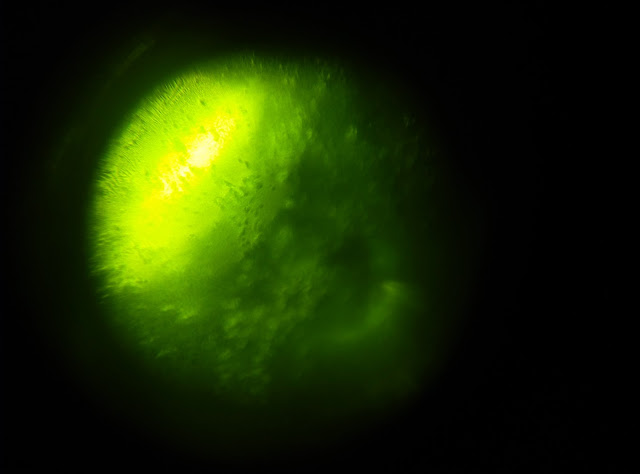

另外,今早我用排卵儀時,

終於第一次看到有洋齒狀的結晶,可惜要拍下照片實在很困難。

總之就是左上角那些長條狀的東西。

雖然數目不是太多,但第一次見到也十分高興。

希望過幾天會看到全洋齒狀結晶吧。